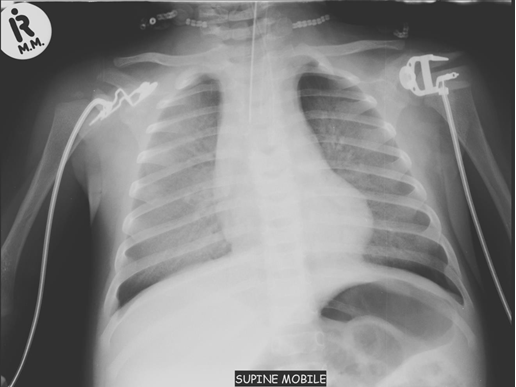

Chest x-ray is not usually diagnostic but may show bilateral diffuse parenchymal infiltrates with a “ground-glass” or reticulogranular appearance, but can be normal or have only mild parenchymal infiltrates. The earliest infiltrates are perihilar, progressing peripherally before reaching the apical portions of the lung.

Presentation: The signs and symptoms of CMV disease often overlap with other infectious processes, therefore, the diagnosis of CMV disease in HIV-infected children should take into consideration clinical presentation and radiological finding along with laboratory testing. CMV pneumonia presents with fever, dyspnoea and hypoxemia. A chest radiograph shows diffuse pulmonary infiltrates (ground glass appearance) as seen in other viral pneumonias and PCP. The isolation of CMV from isolates including BAL does not prove that the child has CMV pneumonia. Co-infection with both PCP and CMV is common.